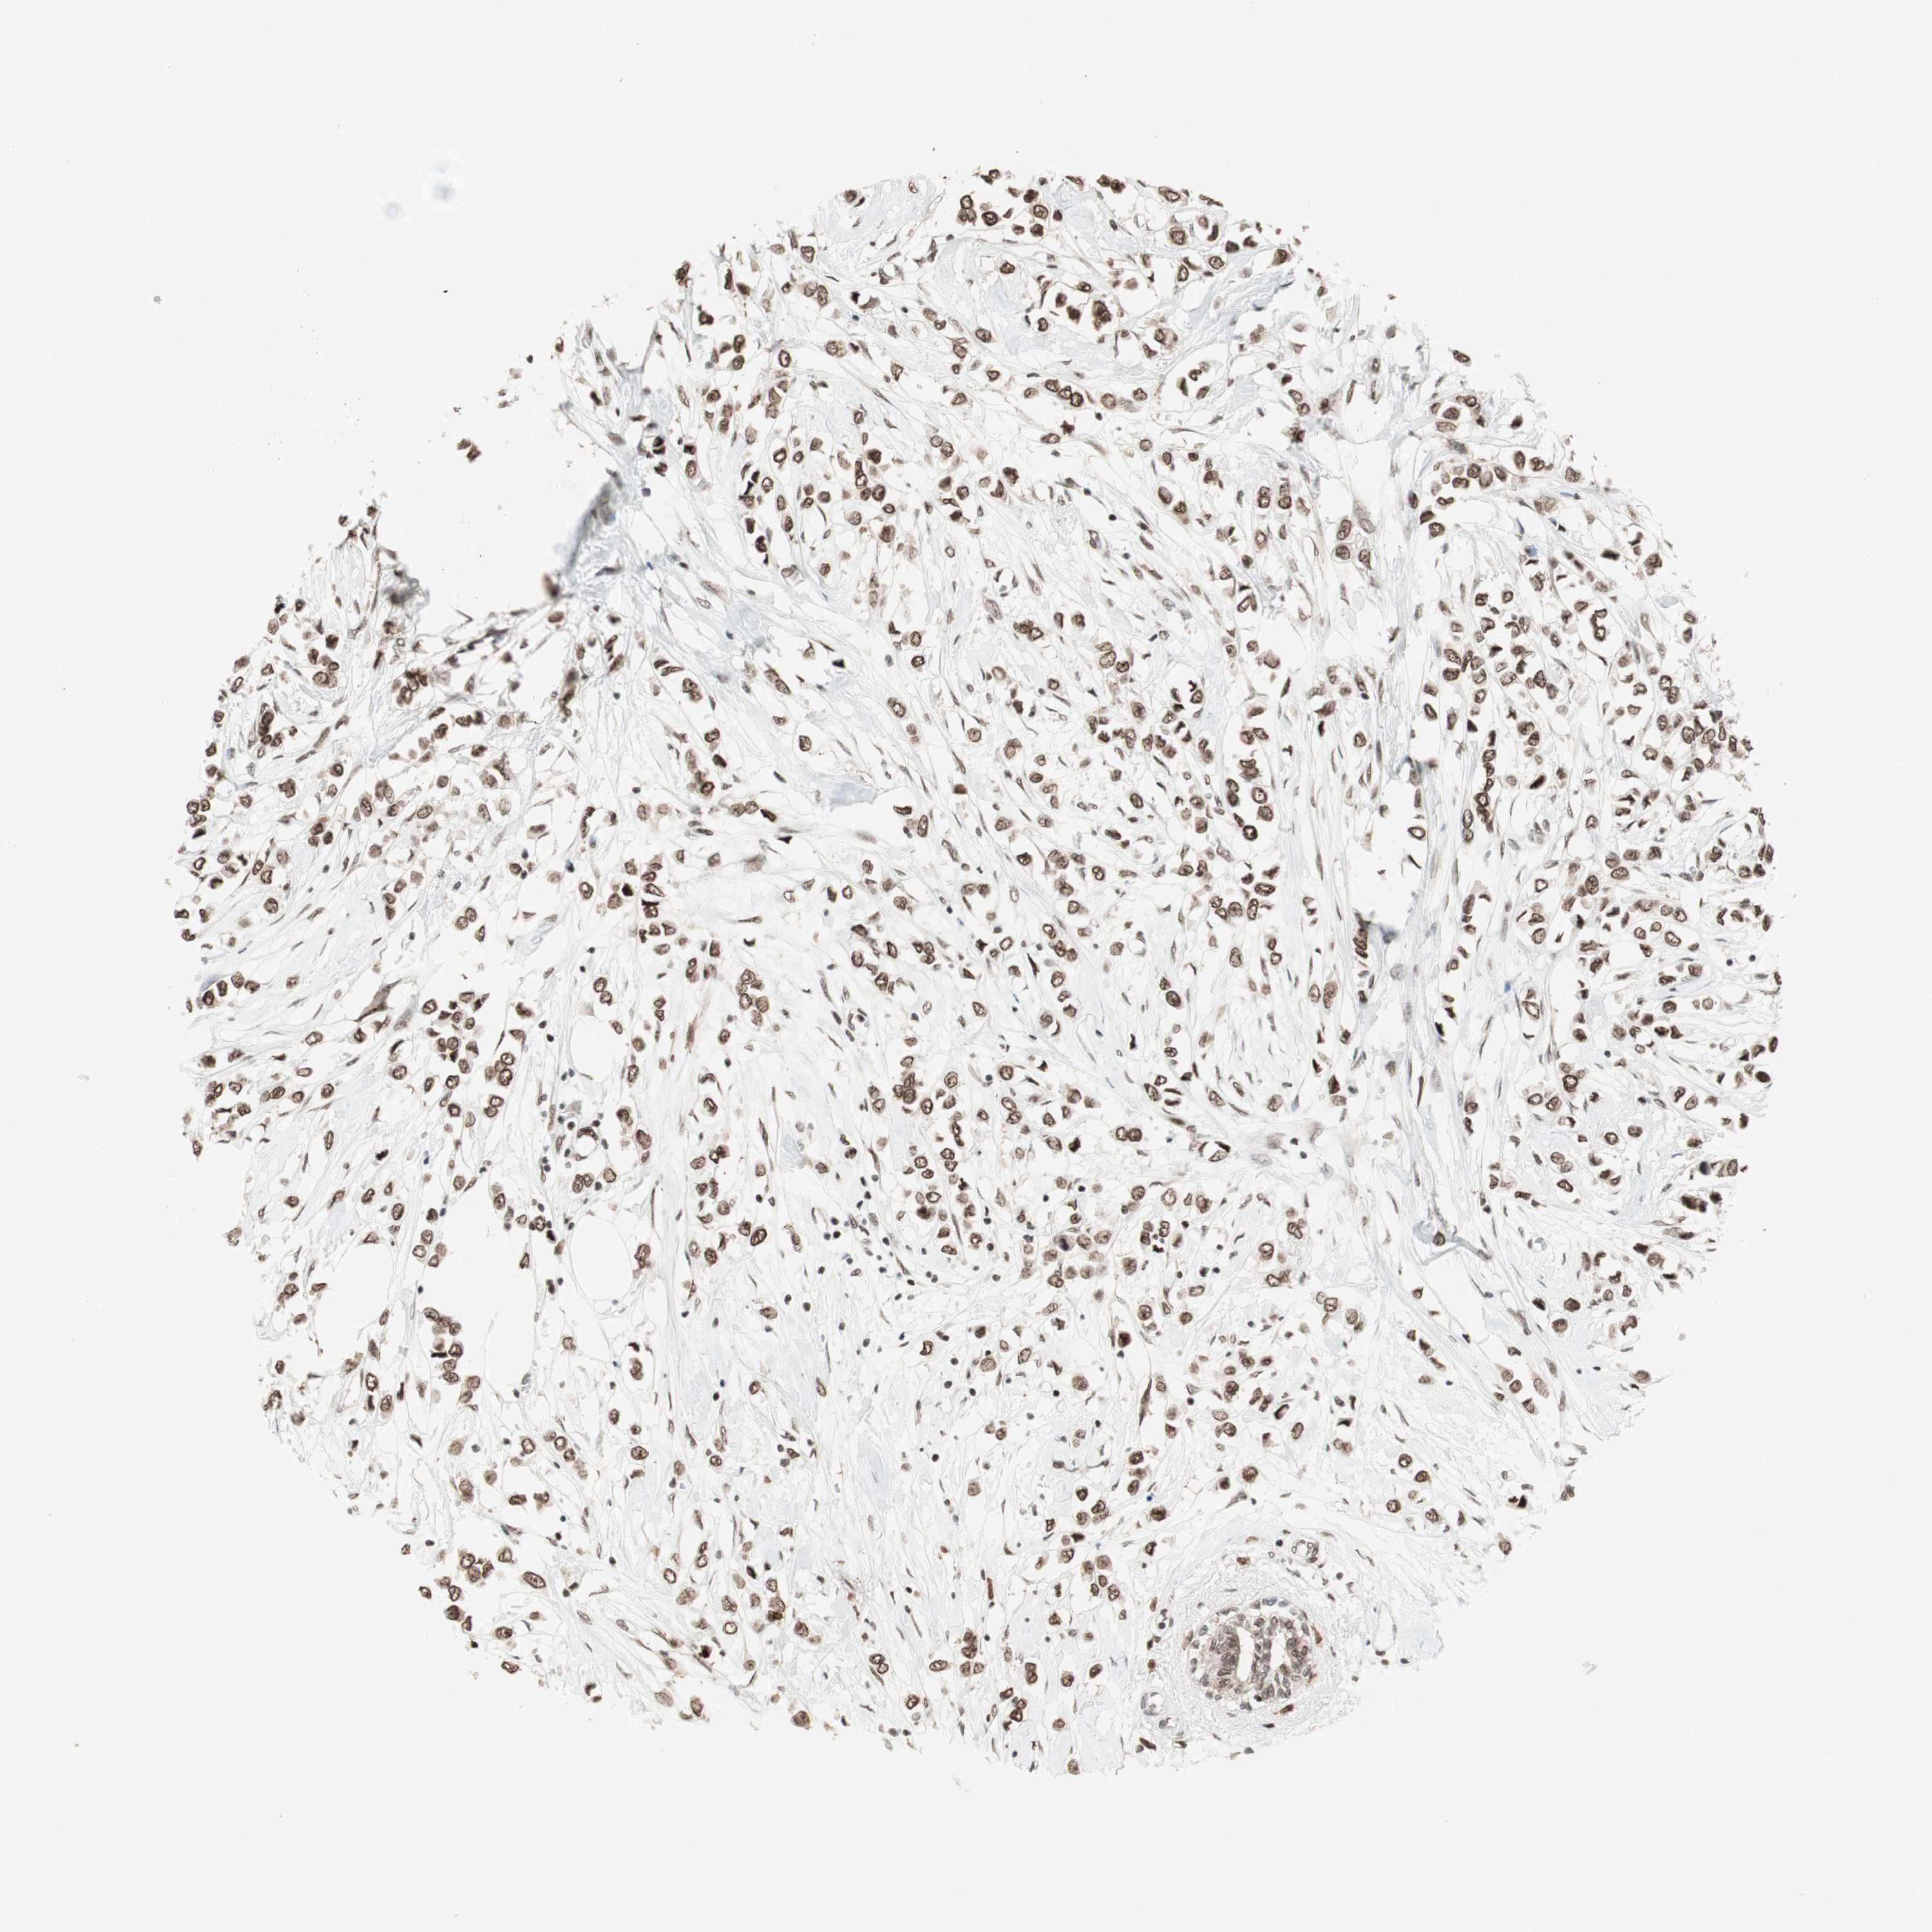

CANCER BREAST CANCER Show tissue menu

BRCA TCGA BRCA VALIDATION PROTEIN EXPRESSION